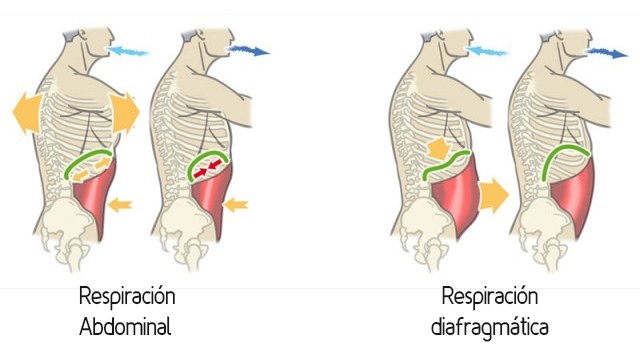

RESPIRACIÓN DIAFRAGMÁTICA

Para empezar, es importante la relajación del paciente, puede estar sentado o boca arriba en cama.

Debemos indicarle al paciente que coloque una mano sobre el tórax y otra sobre la barriga. Una vez las manos estén colocadas le pedimos que respire normal.

|

| Tipos de respiración |

El paciente notará como se mueven sus manos y, dependiendo de cada persona, estos movimientos serán de una forma o de otra. Por lo general, la gente suele utilizar más el tórax para respirar, por lo que su mano se elevará más en esta zona que en la barriga (abdomen).

El objetivo es fortalecer el diafragma.

¿Cómo se hace?

Inhalamos por las fosas nasales para que el aire se caliente, y se exhala por la boca.

Para ayudar al paciente se realiza respiración asistida en la que los fisioterapeutas ayudan el movimiento del diafragma.

Es importante indicarle al paciente que se centre en que todo el aire vaya a la barriga, como si se quisiera tocar con la barriga el techo.

Al principio puede ser complicado, pero si se realiza varias veces al día, el paciente conseguirá realizar este tipo de respiración sin problema y ganará en calidad de vida.